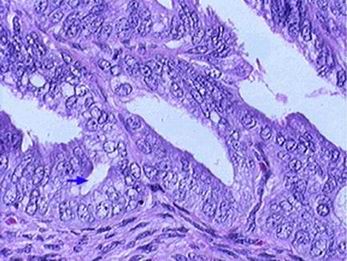

Adenokarcinom čípku /susp. HPV/